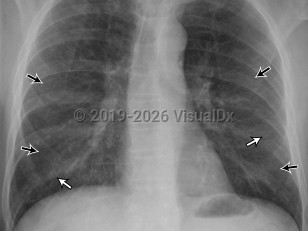

EVALI

COVID-19